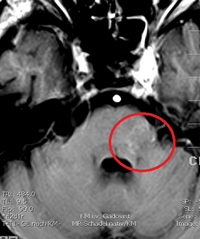

Das linke Bild zeigt einen Lungentumor vor der Cyberknife Behandlung. Der Tumor wurde für die robotergeführte Echtzeitatemsteuerung mit einem kleinen (5 mm) Marker versehen. Das rechte Bild zeigt das Ergebnis 2 Wochen nach der einmaligen Cyberknifebehandlung. Der Tumor ist bereits deutlich kleiner als vor der Behandlung und zentral zerstört.